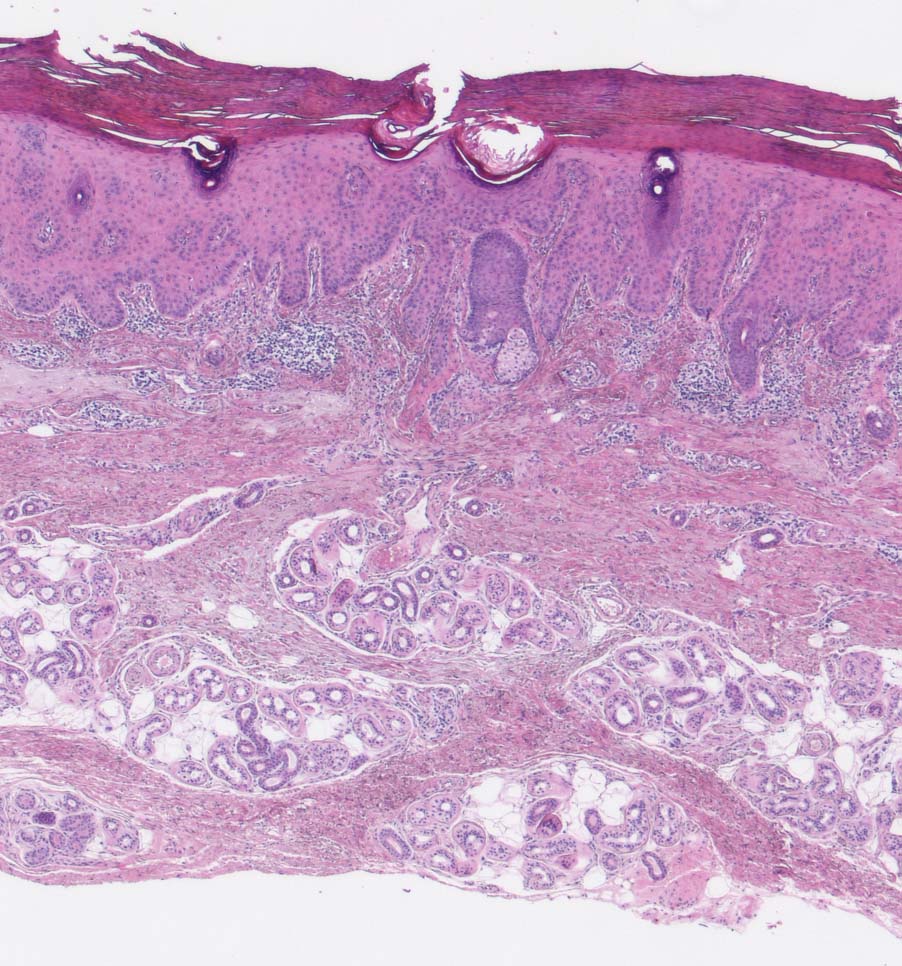

Solare Präkanzerose (Keratose) hyperkeratotischer Typ

Haut, Hand palmar, Finger

Hyper-parakeratotisch verhornende akanthotisch verbreiterte Epidermis. Abblassung des Plattenepithels und Dysplasie in den basalen Abschnitten der Epidermis. Deutliche solare Elastose der Dermis.

Histologie

25